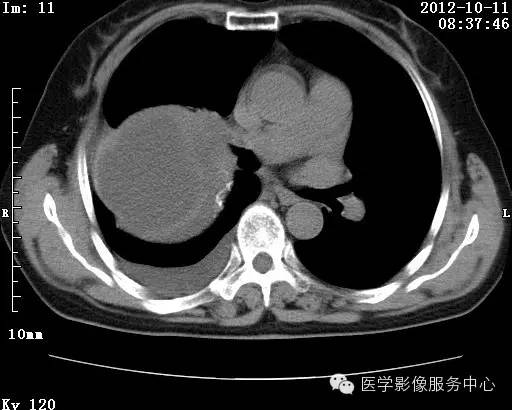

【病例】右肺巨大错构瘤1例CT影像表现

病史:女 65岁咳嗽咳痰 右肺巨大肿块就诊。

错构瘤的主要组织成分包括软骨、脂肪、平滑肌、腺体、上皮细胞,有时还有骨组织或钙化。错构瘤一般为实质致密的球形、卵圆形,也可以是分叶状或结节状,大多数直径在3cm以下。

错构瘤的发病年龄多数在40岁以上,男性多于女性。 绝大多数错构瘤(约80%以上)生长在肺的周边部,紧贴于肺的脏层胸膜之下,有时突出于肺表面。其特征钙化为爆米花样钙化,内有脂肪软骨成分等等。最常见的部位是胸膜下肺实质内,其次为主支气管或肺叶、肺段支气管内。

瘤内出现“爆米花样钙化”是诊断的主要指标之一。早期的点状、斑片状及结节状钙化 随时间增加钙化数量及范围会增加,最终可能演变 为爆米花样钙化;

另一项主要指标是瘤测得脂肪成分是诊断错构瘤。